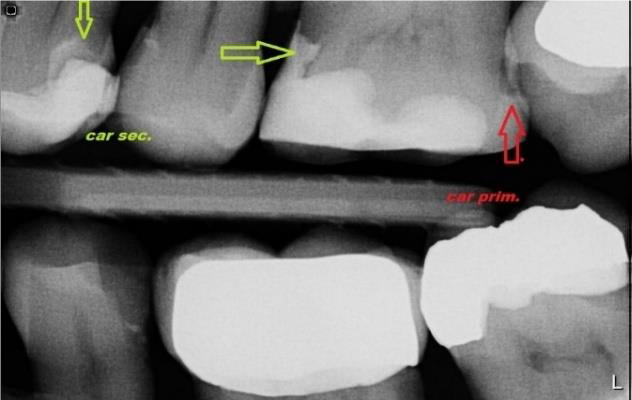

Nový pacient je nejprve objednán na vstupní vyšetření. Během první prohlídky vyšetříme stav Vaší dutiny ústní, zubů a parodontu. Při vyšetření jsou zhotoveny RTG snímky. Nejčastěji zobrazovaným patologickým jevem v ordinaci zubního lékaře je zubní kaz. Včasná diagnostika je zásadní pro rozšíření kazu a následnou sanaci. Odhalení demineralizované skloviny v aproximálních prostorech je především v začátku kazivého procesu možné pouze pomocí rtg snímku. Rovněž sekundární kazy jsou bez snímku většinou nerozpoznatelné. Zubní kaz se na diagnostickém snímku jeví jako tmavší stín právě kvůli demineralizaci zubní tkáně.